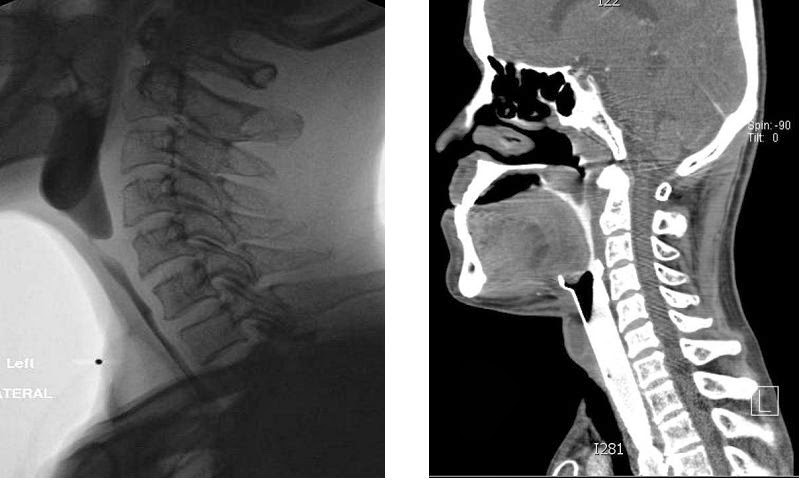

Swallow test radiographs of a high pharyngoesophageal stricture after laryngopharyngectomy